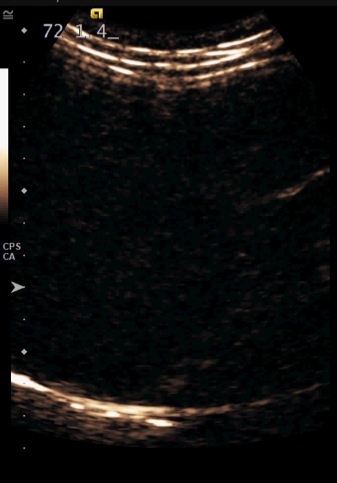

Using Siemens Healthineers ultrasound equipment, these bubbles can be imaged in two distinct contrast-based imaging modes: contrast pulse sequencing and contrast harmonic imaging.

According to Brian, “CPS has a three-pulse sequence that allows us to get deeper into the body. You can see the bubbles a little quicker and they look bigger than they would in the alternate mode. It’s going to provide a better penetration of the ultrasound, making it ideal for most scans involving adults.”

“CHI gives us a higher resolution image for evaluating smaller lesions or lesions with smaller vessels,” said Brian.